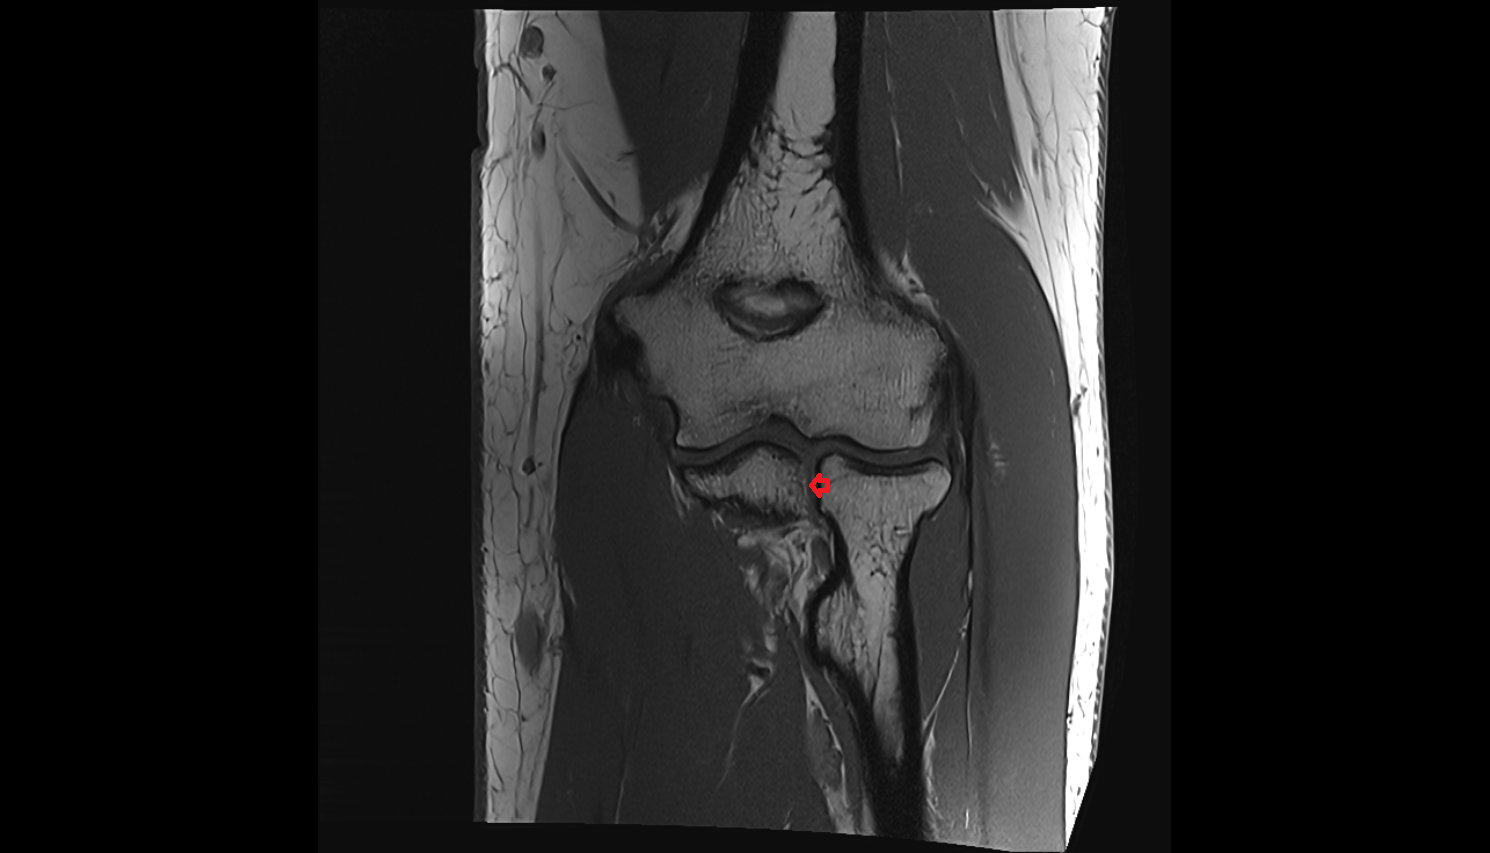

- Knee Joint

- Elbow joint

- Medial collateral ligament complex of elbow (ulnar collateral ligament)